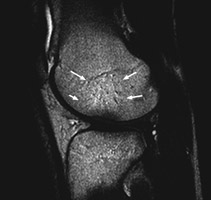

Sagittal T2 weighted and proton density images which reveal complete tear of the ACL with mild increase in marrow signal in the adjacent osseous structures. The bone bruises, as evidenced by increased signal within the marrow, is likely caused by anterior subluxation of the tibia at the time of tear of the ACL accompanied by impaction of the middle portion of the lateral femoral condyle against the posterior portion of the lateral tibial plateau. Signal intensity abnormalities are probably secondary to edema, hemorrhage, and microfracture.

T2W - Click on the image for a larger versionAProton Density - Click on the image for a larger versionB